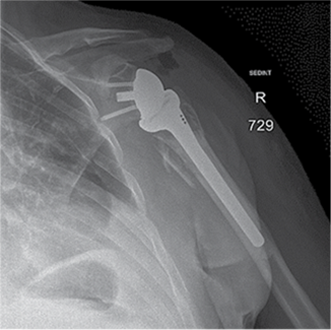

Figure 3. X-ray after shoulder arthroplasty

In a subsequent consultation, it was decided to perform shoulder arthroplasty 11 days later using reverse prosthesis (Delta Xtend, DePuy Synthes) with tuberosity fixation.